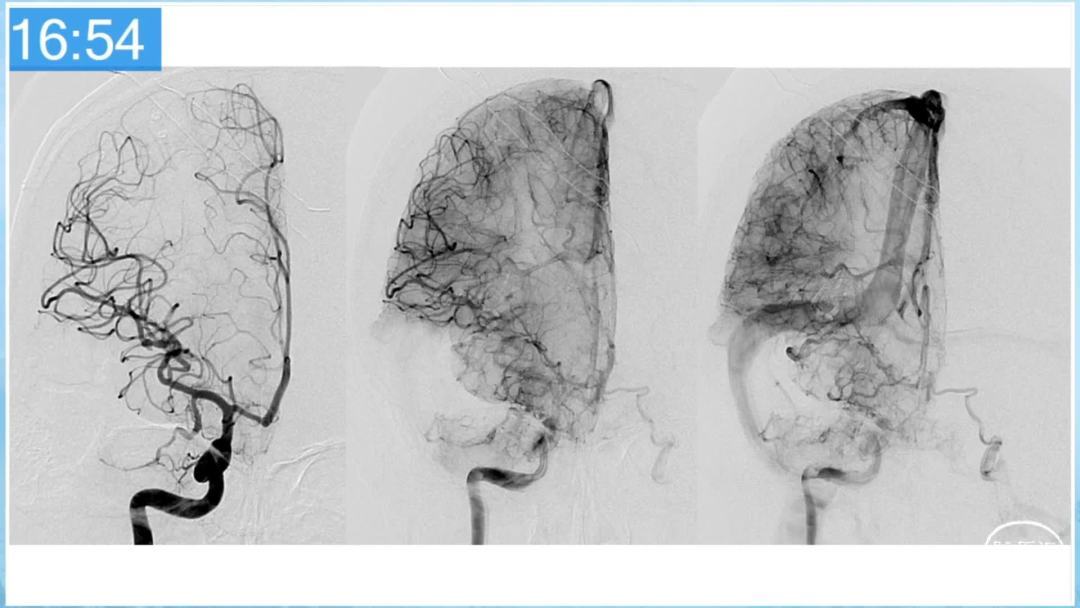

合理的复合平台下的综合治疗,针对每一个病变对应不同方法安全性分析,不预设、不排斥,每种技术发挥到最佳,互相保障。

本期为大家特别分享:空军军医大学唐都医院邓剑平教授的精彩会议内容《颅内动静脉畸形的复合手术治疗》,欢迎大家阅读和分享!